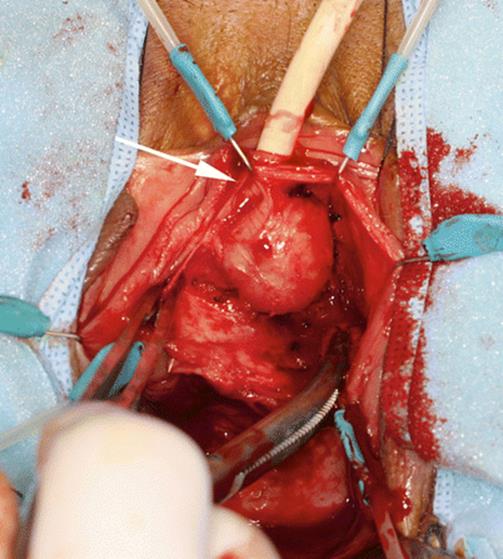

8.3 Ectopic Ureterocele Presenting as a Vaginal Cyst

The patient, 23 years old, presented with difficulty in emptying the bladder, recurrent urinary infection, and distal urethral pain. Figures 8.11, 8.12, 8.13, and 8.14 illustrate the finding of an ectopic ureterocele. The patient had a side-to-side anastomosis of the ureters, with ligature of the affected ureter. The urethral cyst and her voiding dysfunction were corrected and she remained asymptomatic.

Fig. 8.11

Physical examination reveals a large, cystic mass emerging from the urethra (arrow)

Fig. 8.13

A voiding cystogram showing a filling defect of the bladder base extending toward the urethra. The arrows delineated the cystic defect